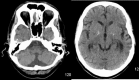

A 48-year-old man was admitted for workup of stroke-like symptoms and generalised tonic-clonic seizures. History and examination revealed that the patient had background diagnoses of type 2 diabetes mellitus, epilepsy and had suffered a temporal lobe infarct 3 years ago. The unusual presentation and physical findings, along with subsequent MRI findings led to a diagnosis of mitochondrial myopathy, encephalopathy, lactic acidosis and stroke-like episodes (MELAS). MELAS is a mitochondrial disorder typified by the aforementioned symptoms, and is typically diagnosed in the first two decades of life.